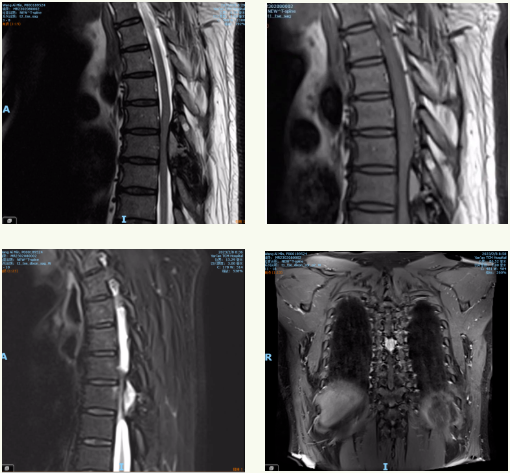

患者告诉神经外科董永军副主任,自己1年前无明显原因出现胸背部疼痛,左侧为主;半年前双下肢发凉,没有做特殊治疗。4月前出现双足麻木、疼痛,逐渐向上发展,并伴有活动无力。咳嗽、大便等增加腹压时上述症状无明显加重,影响了睡眠。于是前往当地医院行胸腰椎MR提示胸7/8平面椎管内占位病变。1个月前双下肢无力、麻木,疼痛明显加重,行走困难,严重影响了日常生活。

在征得患者及家属同意后,北京专家张嘉教授,神经外科田德洲主任、董永军副主任通力协作,成功为患者实施了后正中入路胸6/7平面椎管内肿瘤切除+椎管扩大减压术。术中棘突及椎板骨化,椎板咬骨钳咬除困难,用超声骨刀切除椎板,形成骨窗,暴露肿瘤。术后病理证实是浆细胞瘤,随后开展预防感染,减轻水肿、结合高压氧、康复理疗等。术后2周患者出院,左下肢肌力4+级,右下肢肌力4级,肌张力略增高,目前双下肢疼痛麻木消失。